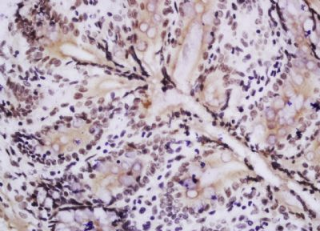

组织/细胞:大鼠直肠组织;4%多聚甲醛固定石蜡包埋;

抗原提取:柠檬酸缓冲液(0.01M,pH 6),15min煮沸,用3%过氧化氢阻断内源性过氧化物酶30min;37℃下阻断缓冲液(正常山羊血清)20 min;

孵育:抗磷酸AMPKα-1(THR183)多克隆抗体,未结合 1:200,在4°C下过夜,然后接合到二级抗体和DAB染色。